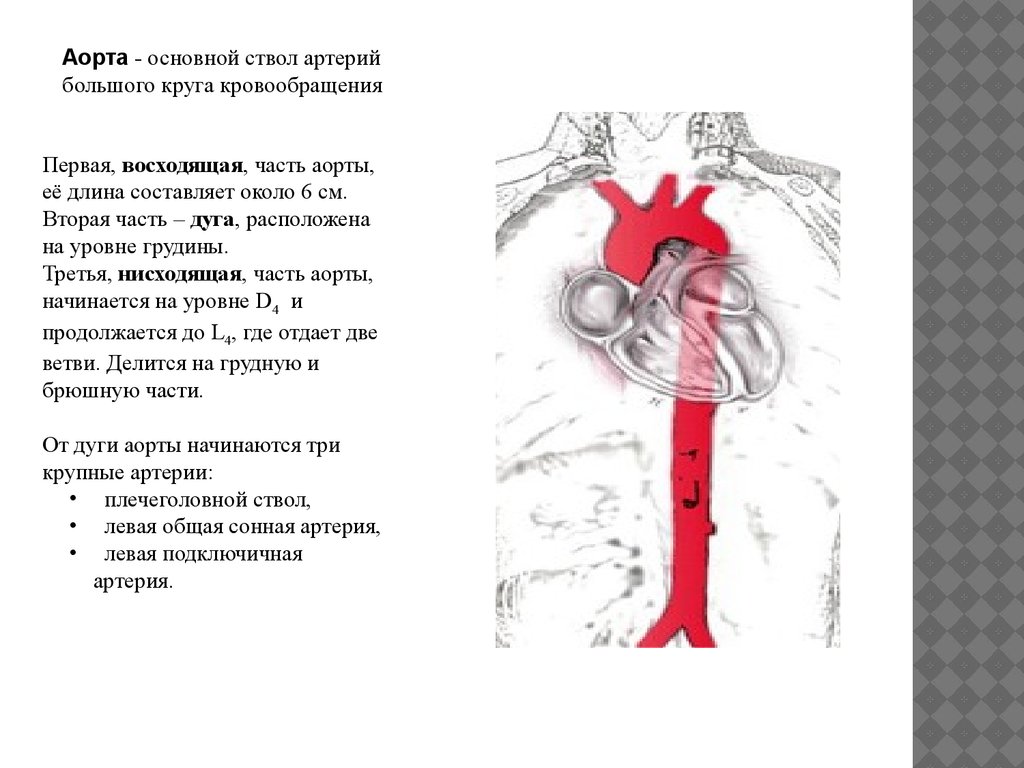

Нормальный диаметр корня аорты: медицинские нормы и отклонения